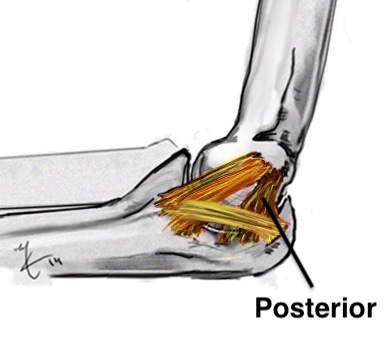

Anatomy of Ulna Collateral Ligament (UCL)

Provides valgus stability

Three components

| Anterior band | Posterior band | Transverse band |

Fan shaped Stabilizes from 90 - 120 degrees |

Medial epicondyle to medial semilunar notch of ulna |